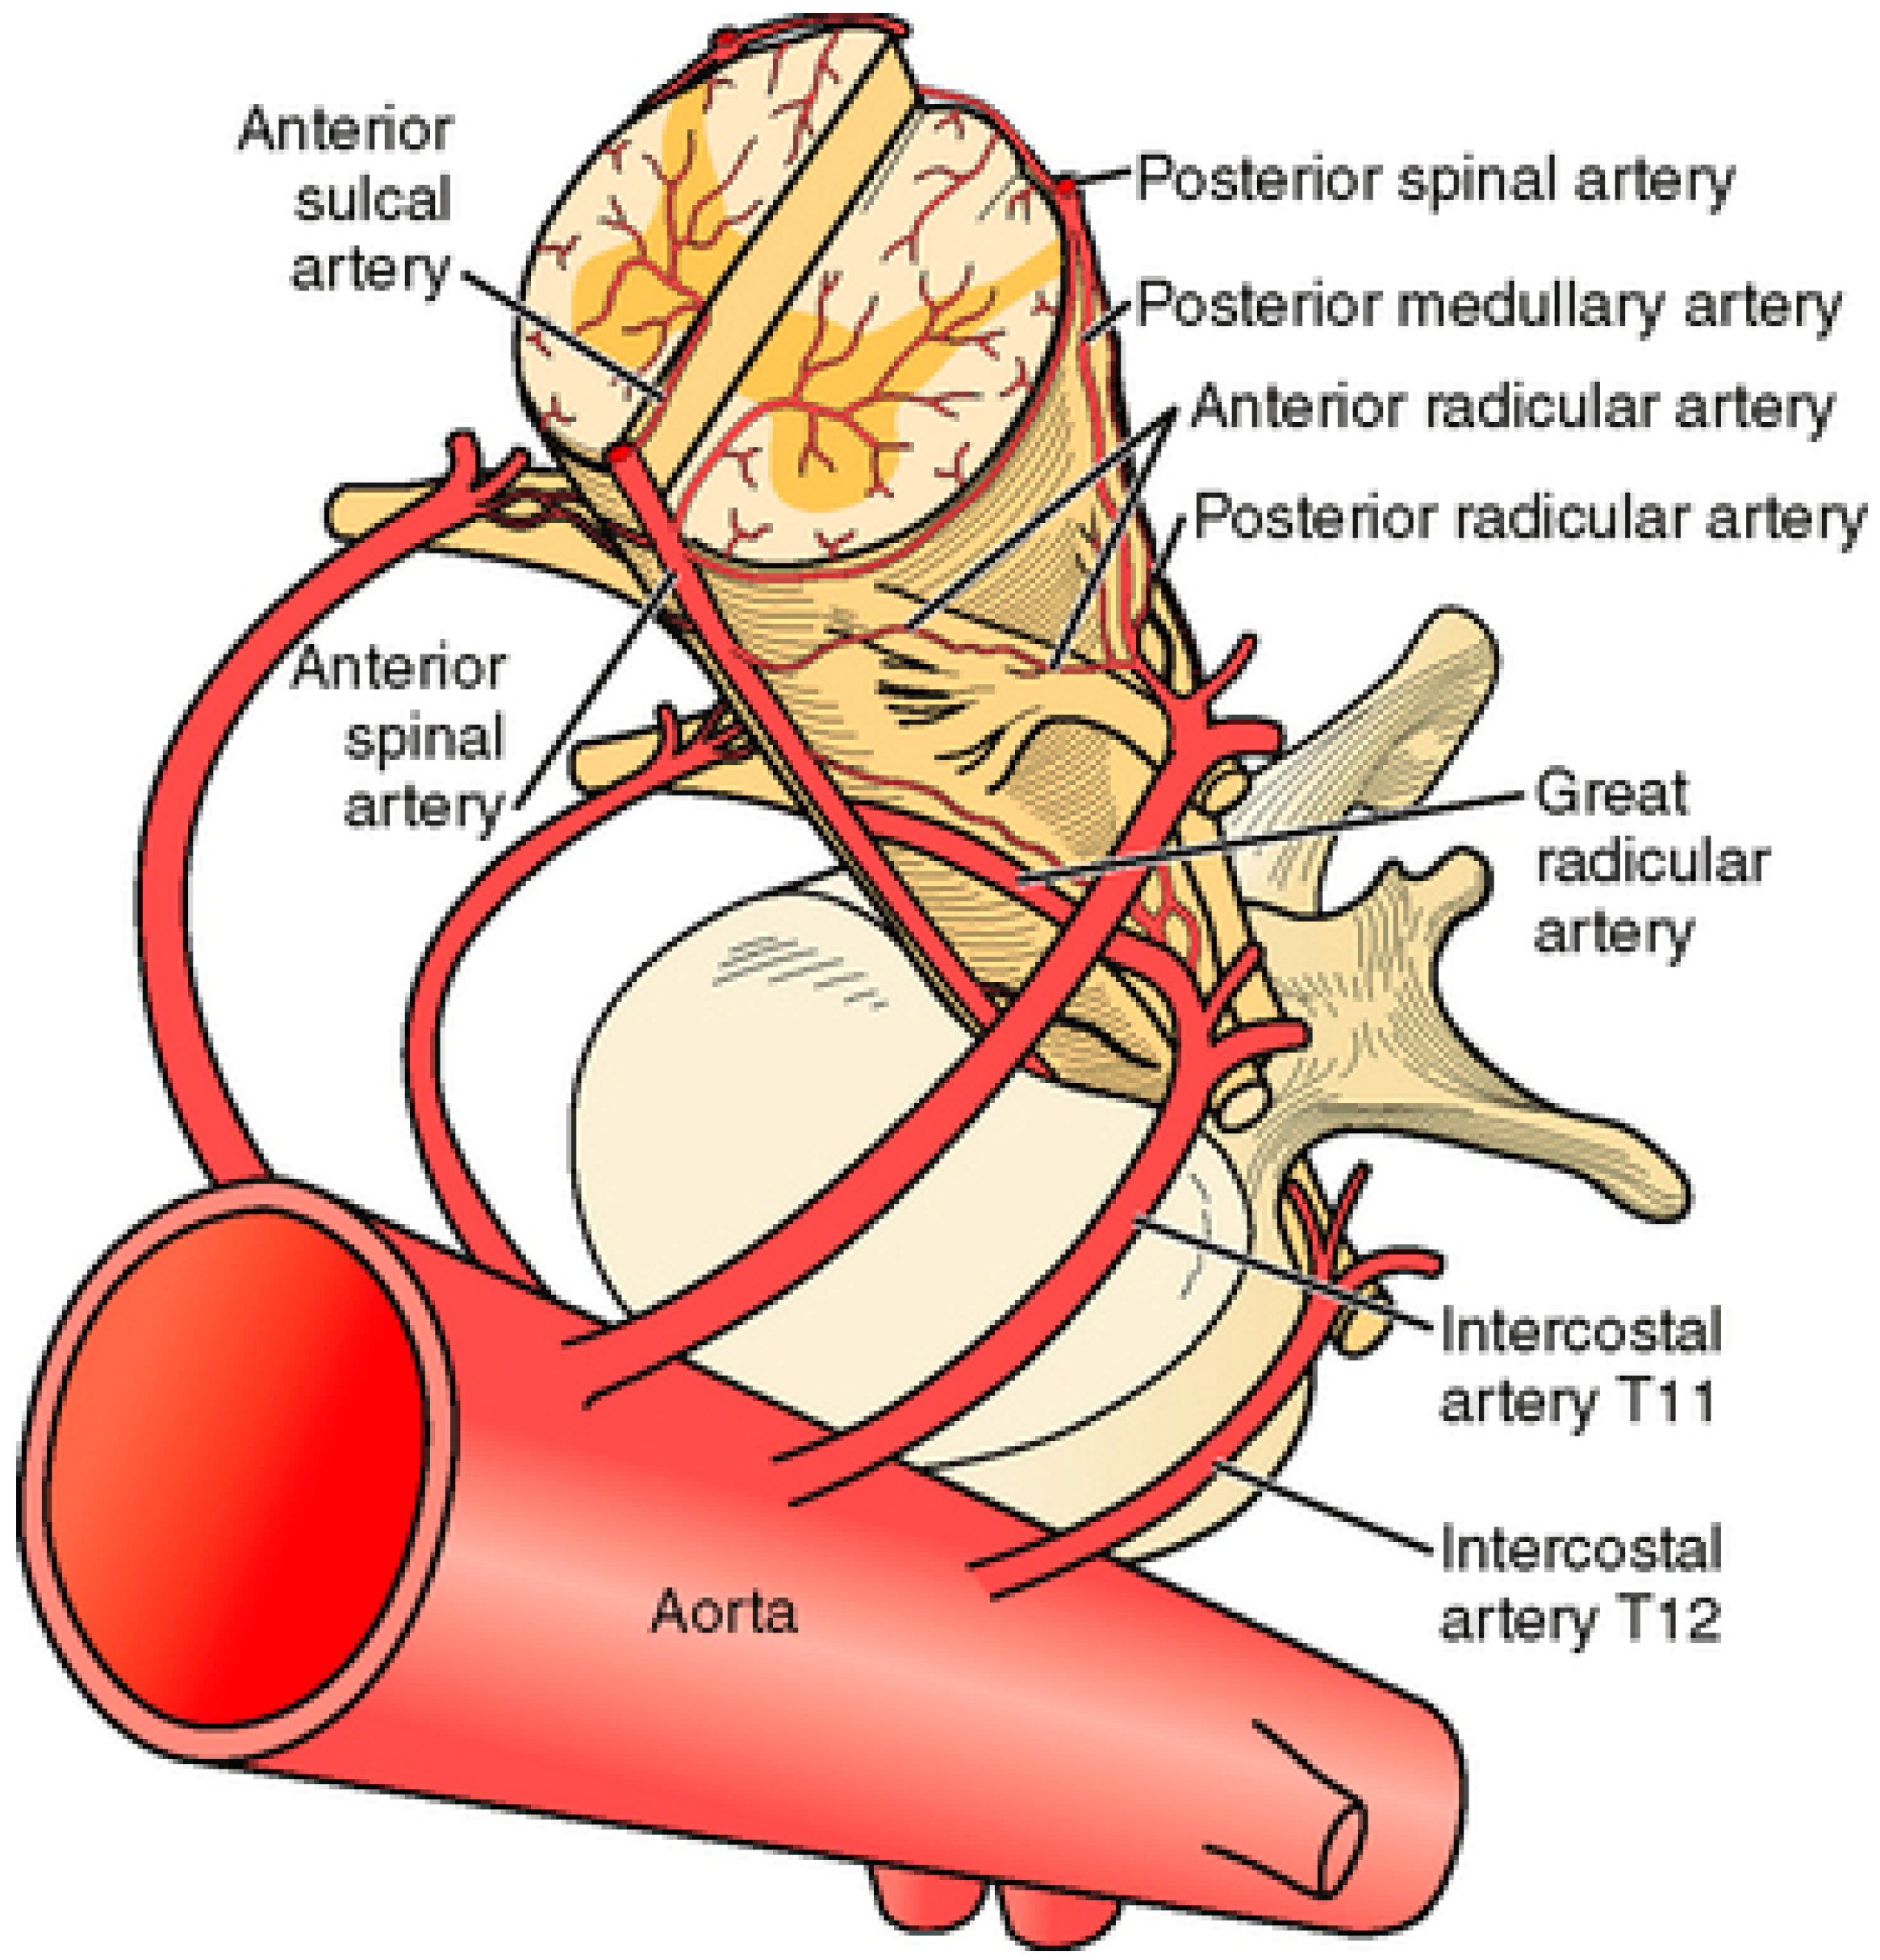

4. Discussion